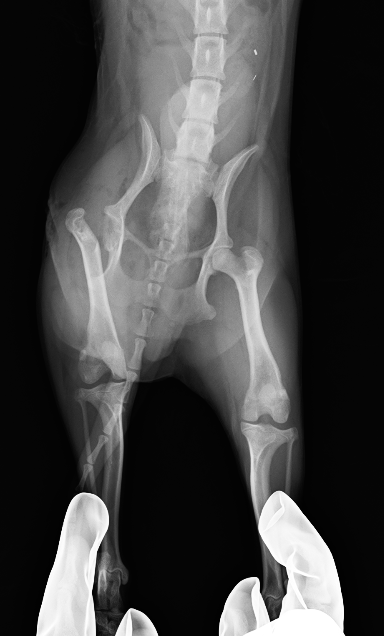

犬

整形外科

大腿骨頭壊死

大腿骨頭壊死とは?

大腿骨頭への血流不全により壊死、変形する病気で、主に若齢の小型犬に多い

症例紹介

犬種

年齢

9ヶ月齢

体重

2.4kg

性別

雄・雌(去勢済/避妊済)

来院のきっかけ

1ヶ月前より右後肢破行・挙上

所見

右後肢大腿骨頭切除

before